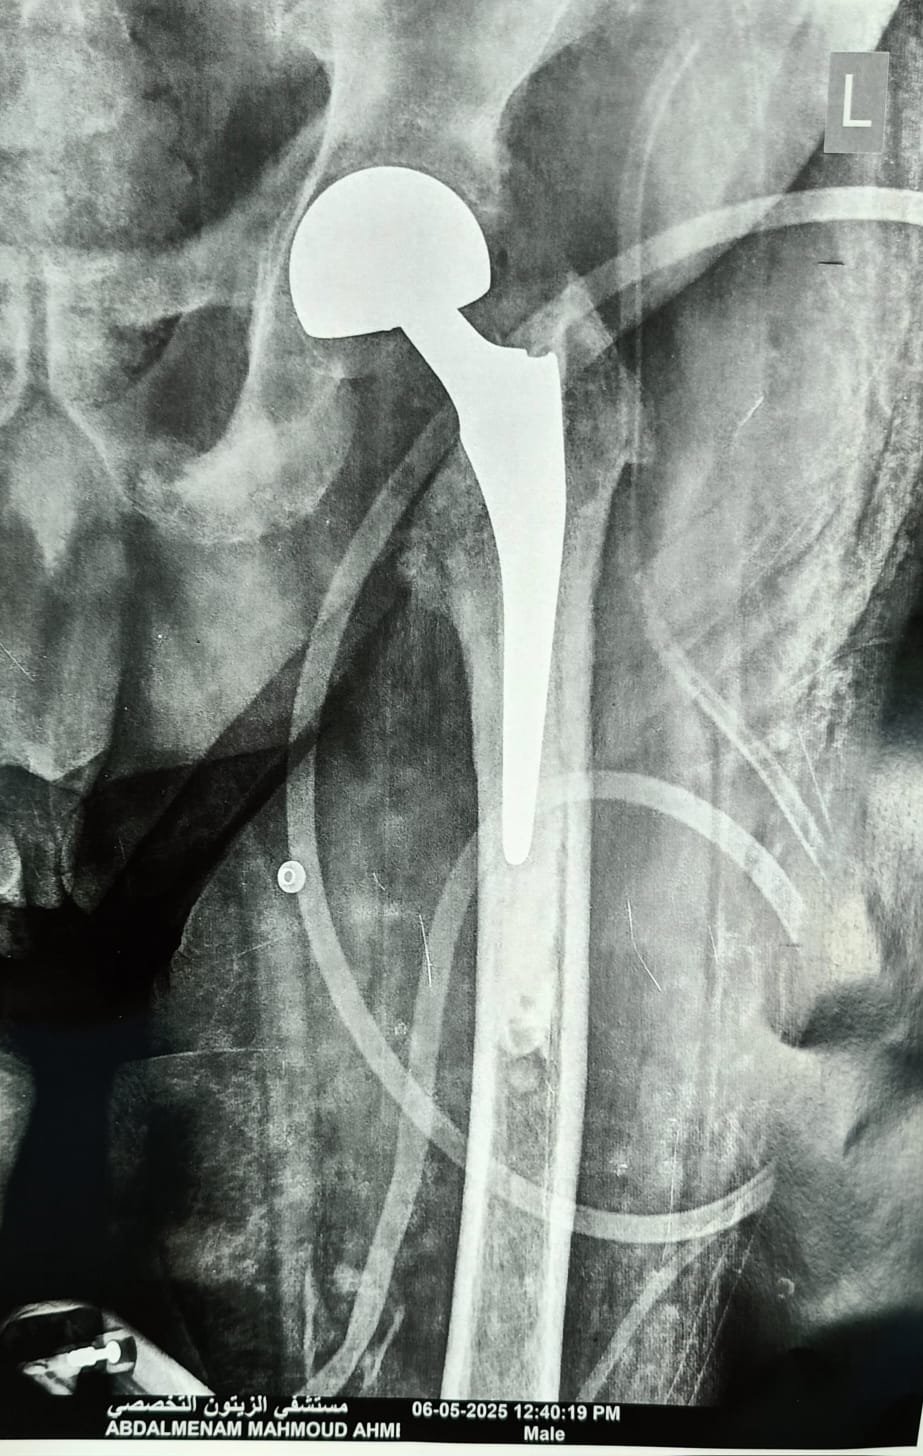

استغرقت العملية وقتًا حساسًا للغاية، نظرًا لحالة المريض الصحية المعقدة، لكنّ الفريق الطبي نجح في تنفيذ الجراحة بكفاءة عالية، مراعين أعلى معايير الجودة الطبية، وهو ما مكن المريض من الوقوف على قدميه بعد يومين فقط، وبدء مرحلة التعافي تدريجيًا.

رغم تعقيد الحالة بسبب انتشار الورم، وضعف عضلة القلب، والأنيميا، وضيق التنفس، قرر الفريق الطبي في مستشفى الزيتون التخصصي خوض التحدي وإجراء عملية تغيير مفصل الفخذ وتركيب مفصل صناعي. وبعد إجراء الفحوصات الدقيقة ومناقشة كافة التفاصيل مع المريض وأسرته، تمت الموافقة بشجاعة وثقة بالله وبالطاقم الطبي.